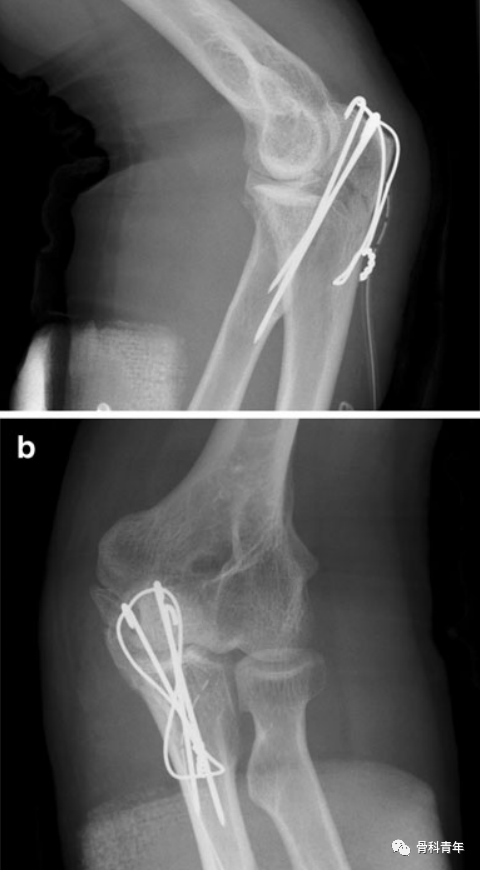

不规范操作示例:病例1:该患者X线显示克氏针过长,远远超出对侧皮质;克氏针不平行,存在交叉;并利用了第三根克氏针。

病例2:该患者X线显示克氏针过长;单结固定;克氏针尾部折弯不够,未有效固定;克氏针穿入关节。